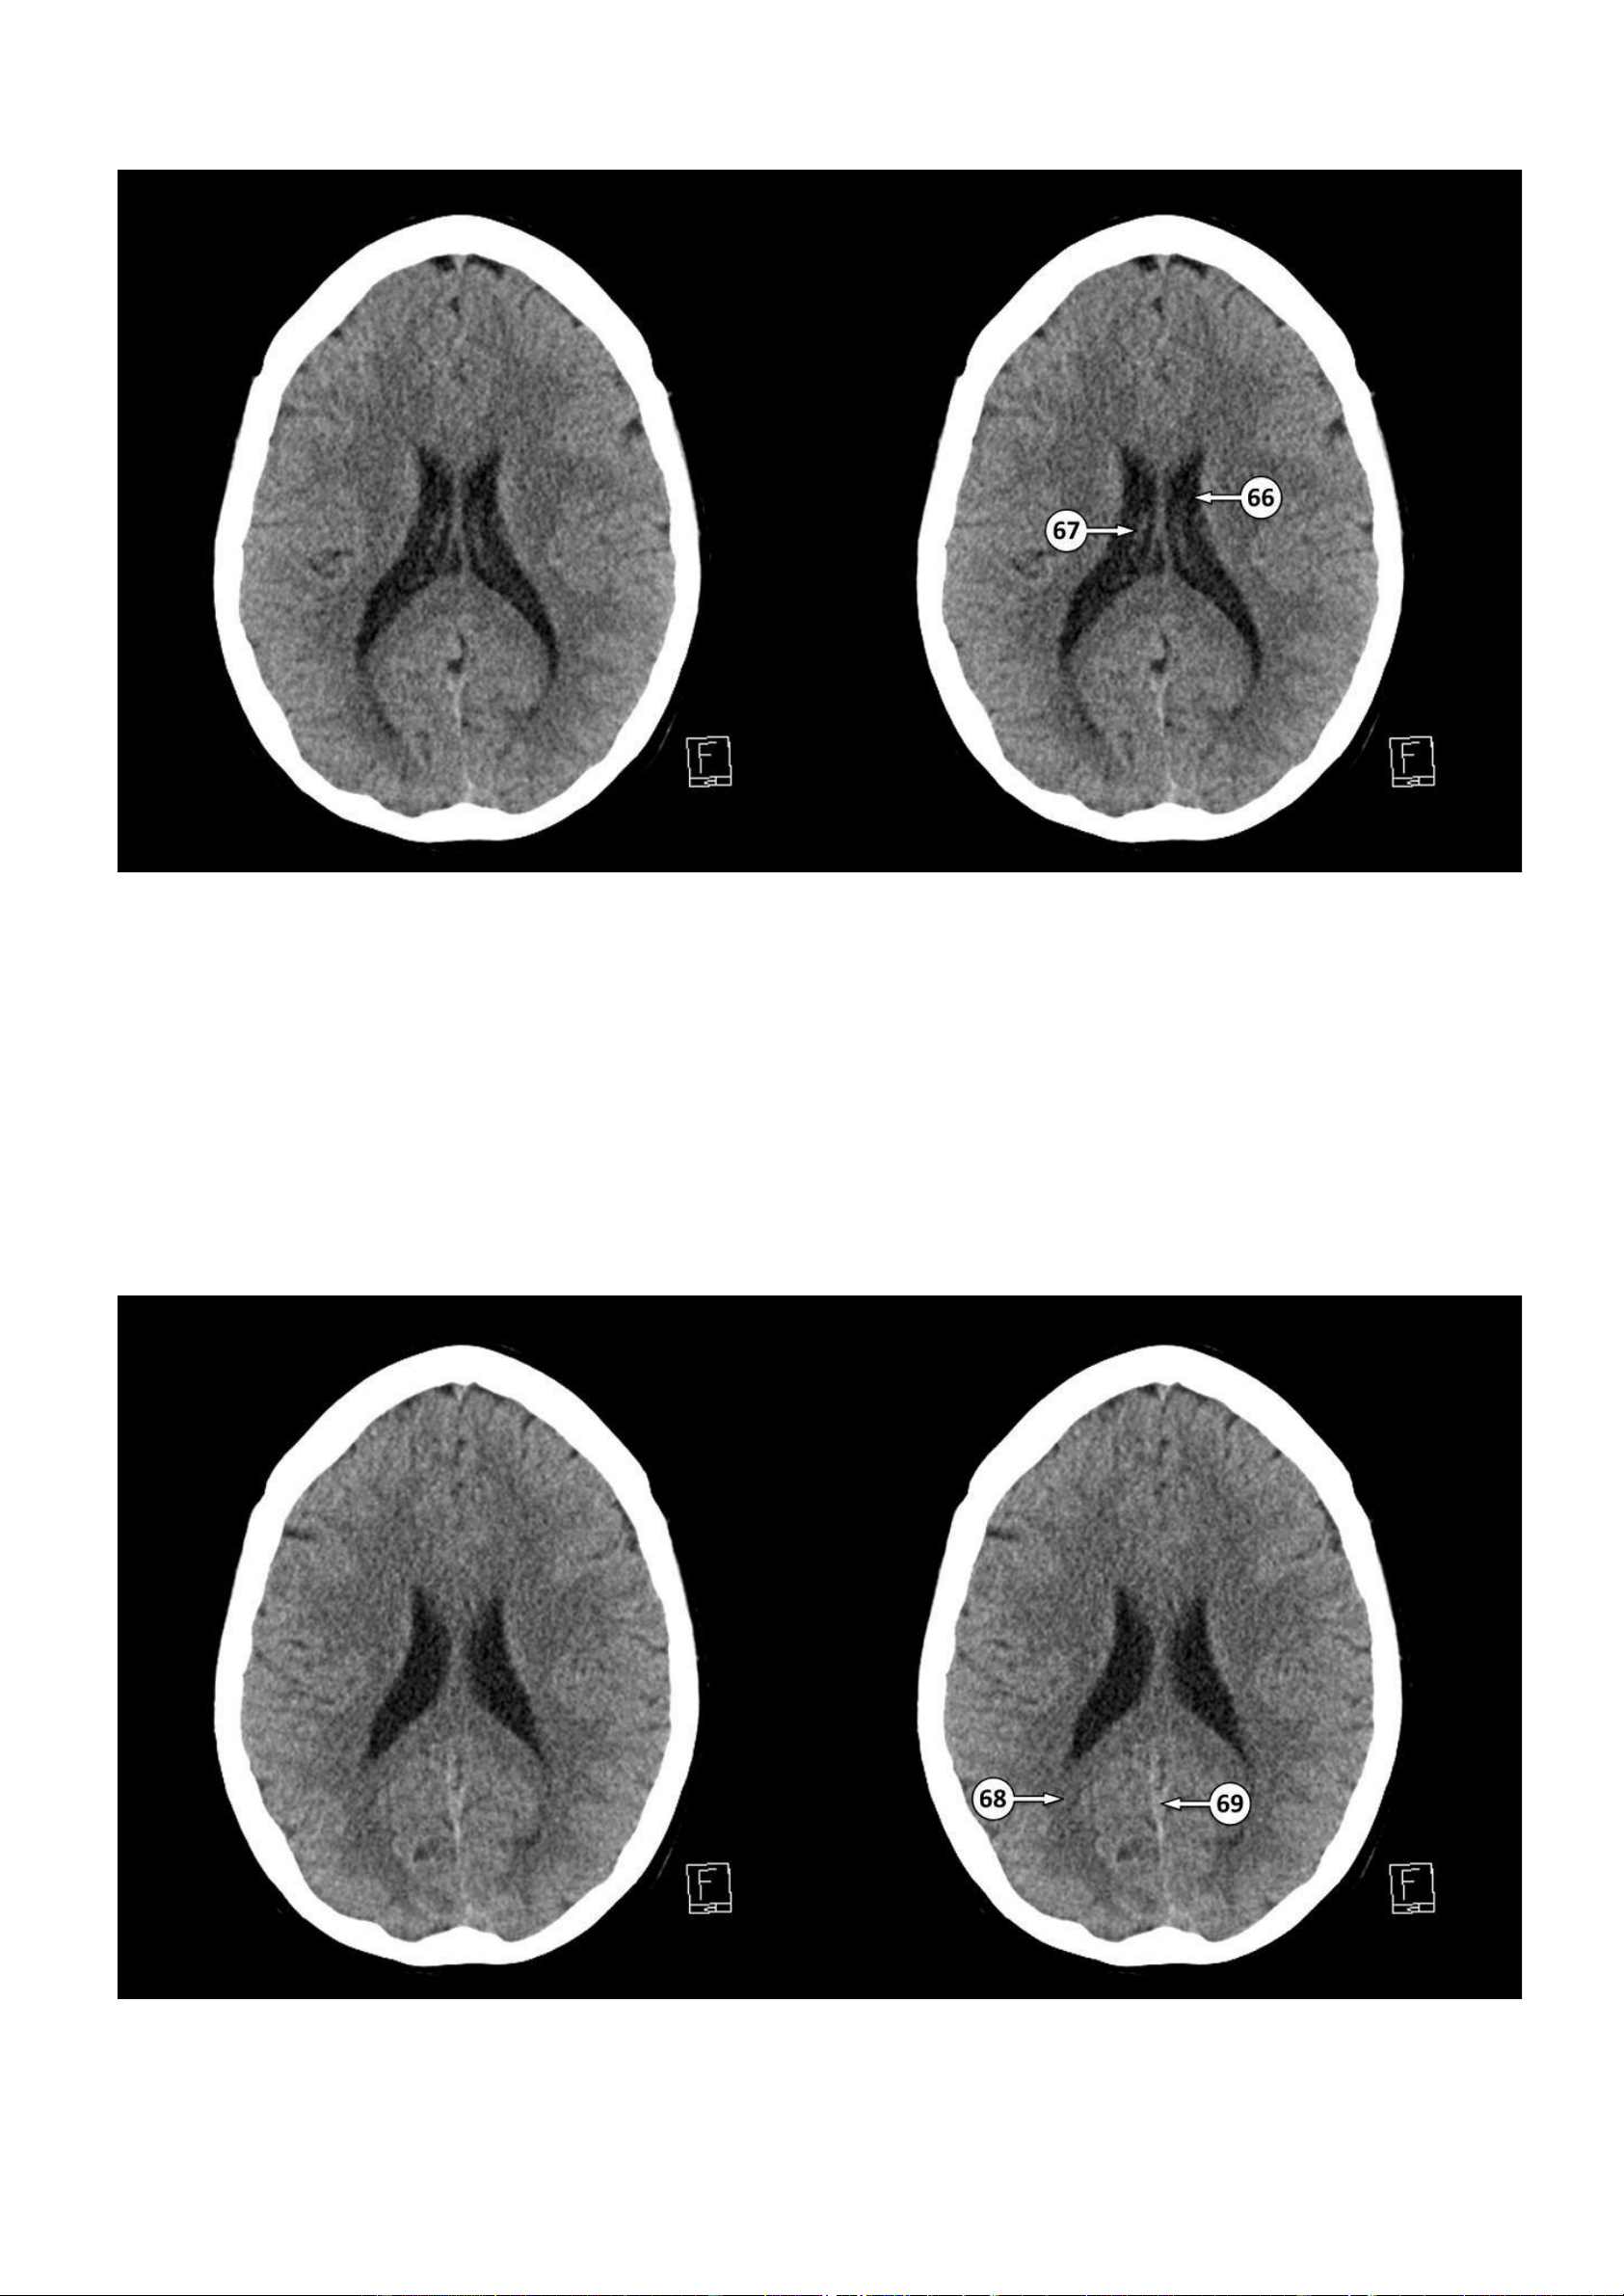

▪ Số 66: Thân của não thất bên

▪ Số 67: Đám rối mạch mạc 68: Bó lớn 69: Xoang dọc dưới lOMoAR cPSD| 22014077